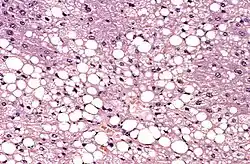

La stéatose hépatique est une lésion du foie correspondant à la surcharge de graisse dans le cytoplasme des hépatocytes.

La stéatose est définie comme l'accumulation de matériel lipidique au sein du cytoplasme des hépatocytes[2]. Ces lipides correspondent principalement à des triglycérides[2].

Il existe deux types de stéatose hépatique aux étiologies bien différentes : la stéatose macro-vésiculaire et la stéatose micro-vésiculaire. La stéatose macro-vésiculaire est la plus fréquente majoritairement associée à la consommation excessive d'alcool. Elle est caractérisée par la présence d'une unique vésicule volumineuse au sein du cytoplasme[1],[2]. La stéatose micro-vésiculaire est plus sévère[1] et correspond à la présence de multiples petites vésicules lipidiques[1].

La sévérité de la stéatose est déterminée histologiquement par le pourcentage en hépatocytes comportant une ou des vacuoles dans leur cytoplasme[1]. On parle de stéatose légère en dessous de 30 %, de stéatose modérée entre 30 et 60 % et de stéatose sévère au-delà de 60 %[1]. Cette mesure ne correspond donc pas à un volume en graisse.